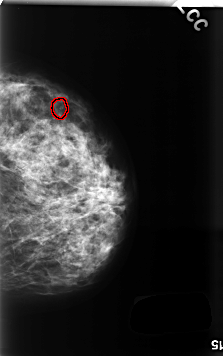

FILE: C_0499_1.RIGHT_CC.OVERLAY

TOTAL_ABNORMALITIES 1

ABNORMALITY 1

LESION_TYPE CALCIFICATION TYPE PLEOMORPHIC DISTRIBUTION CLUSTERED

ASSESSMENT 4

SUBTLETY 3

PATHOLOGY BENIGN

TOTAL_OUTLINES 1

BOUNDARY